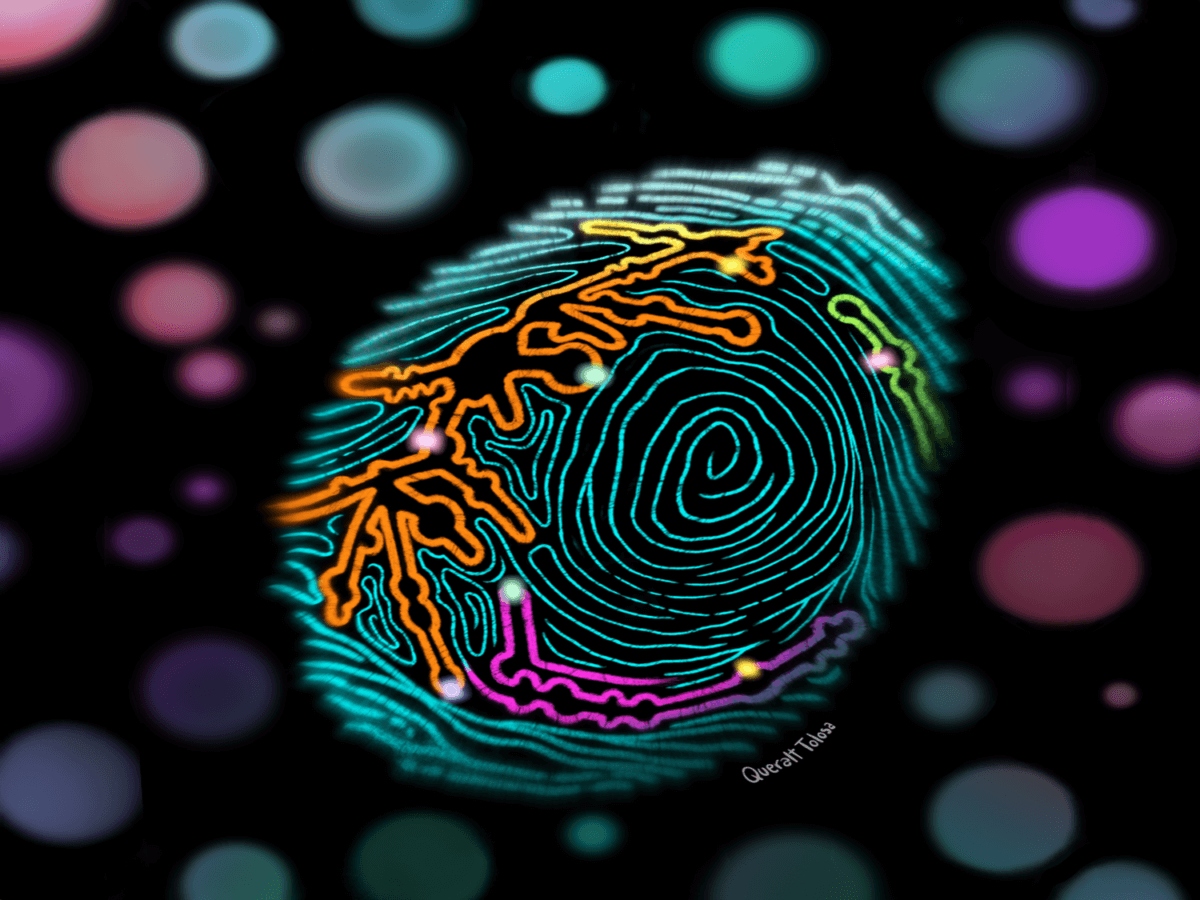

Έλληνας ερευνητής αναπτύσσει προγνωστικά εργαλεία για τον καρκίνο του πνεύμονα και του παχέος εντέρου

27/01/2025 - 14:30